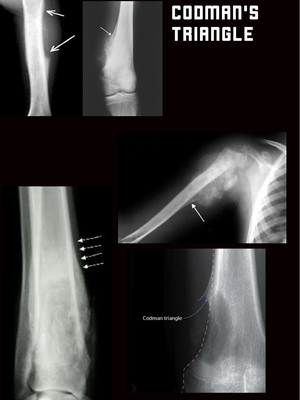

Codman triangle is the triangular area of new subperiosteal bone that is created when a lesion, often a tumour, raises the periosteum away from the bone. A Codman triangle is not actually a full triangle. Instead, it is often a pseudotriangle on radiographic findings, with ossification on the original bone and one additional side of the triangle, which forms a two sided triangle with one open side. The Codman triangle may be seen with aggressive lesions: osteosarcoma Ewing sarcoma Osteomyelitis active aneurysmal bone cyst giant cell tumour metastasis Chondrosarcoma (especially juxtacortical chondrosarcoma) malignant fibrous histiocytoma.